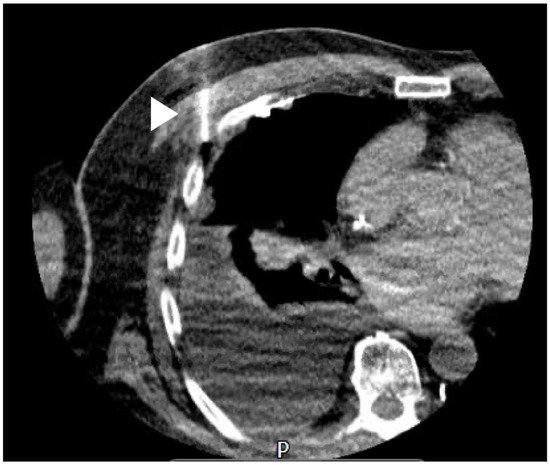

14. CT